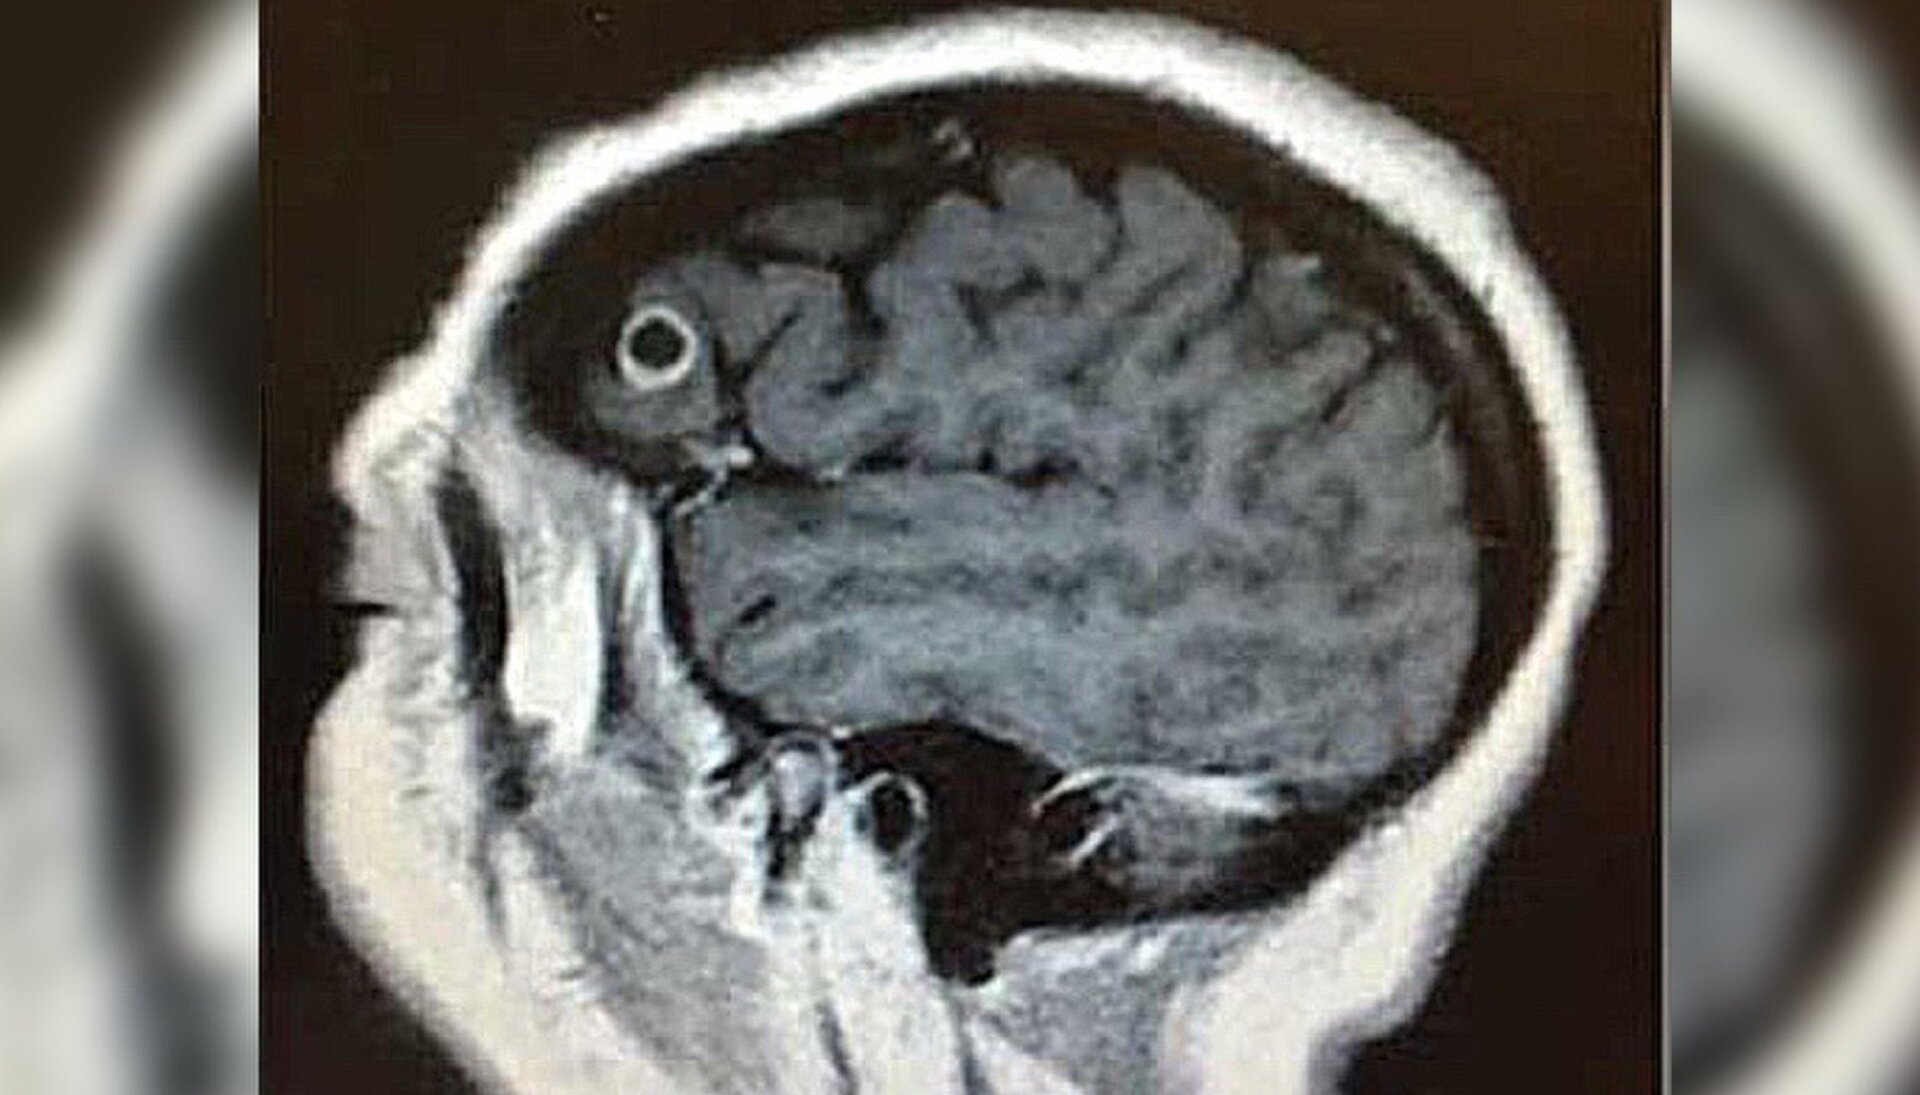

Tras una posterior resonancia magnética, llegaron las malas noticias: tenía un tumor cerebral, o eso es lo que los médicos pensaron hasta que comenzó la cirugía y se descubrió lo que tenia deslizándose alrededor de su cerebro.

Aquello no era un tumor en el lóbulo izquierdo como se esperaba. Descubrieron un gusano largo y liso que le salía del cerebro. Normalmente, tal hallazgo es motivo de preocupación, pero como el diagnóstico inicial fue un tumor cerebral fatal, la tenia se convirtió en motivo de celebración.